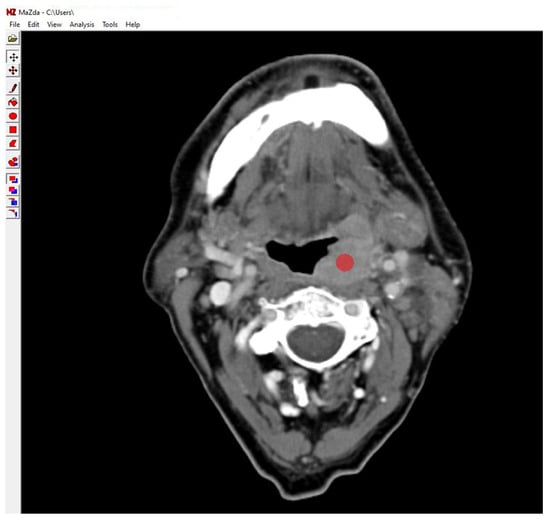

2.6. Texture Feature Extraction